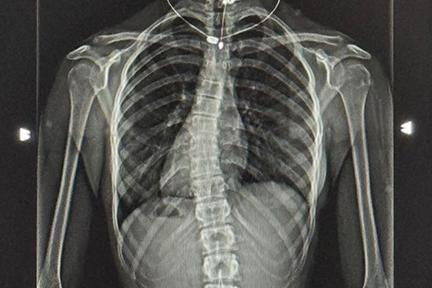

Since the age of three, Mikaela has been passionate about ballet. However, her world turned upside down last year when she was diagnosed with scoliosis. Determined to overcome this challenge, she sought treatment and support from her medical team, family, and friends. With their encouragement and her own resilience, Mikaela not only managed her back pain, she also discovered renewed strength and determination.

At Joe DiMaggio Children's Hospital Spine Care, Nurse Practitioner Kimberly introduced Mikaela to a treatment plan that included physical therapy and gyrotonic exercises—a method that uses three-dimensional, whole-body movements to improve strength, flexibility, and coordination.